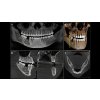

Skutečný univerzál ve své třídě

Vysoce kvalitní 2D / 3D rentgenové zařízení s komplexní nabídkou služeb pro každou praxi. Ať už jen jako 2D zařízení nebo včetně 3D modulu - Orthophos S je spolehlivým partnerem a je optimalizován pro každodenní úkoly. Jeho CsI senzor s funkcí automatického zaostřování zajišťuje jasný obraz i v anatomicky obtížných případech. Patentovaný blok okluzního skusu automaticky polohuje pacienty. Pro použití v ortodoncii je Orthophos S k dispozici také s volitelným cephalometrickým ramenem. A protože společnost Dentsply Sirona myslí i na zajištění budoucnosti, lze cephalometrické rameno kdykoli dovybavit.

Vidět více s jistotou: pro získání vysoké úrovně ostrosti je nezbytné správné zaostření. Čelist musí být v ostré vrstvě obrazu přístroje. Proto Orthophos vytvoří během jedné otáčky několik tisíc jednotlivých snímků a automaticky rozpozná oblasti, ve kterých je čelist optimálně umístěna. Ty se zobrazí ve výsledném snímku - bez jakýchkoli manuálních mezikroků.

Orthophos S 3D nabízí možnost instalovat kdykoli kefalometrické rameno. Navíc, aby bylo jisté, že se přístroj vejde do vaší rentgenové místnosti, je možné rameno namontovat na pravou nebo na levou stranu jednotky. Za použití příslušného senzoru získáte laterální a symetrické předozadní ap/pa kefalo snímky i snímky zápěstí. V případech retinovaných zubů se můžete vrátit zpět k výhodám 3D rentgenů a stanovit jejich přesnou lokaci.